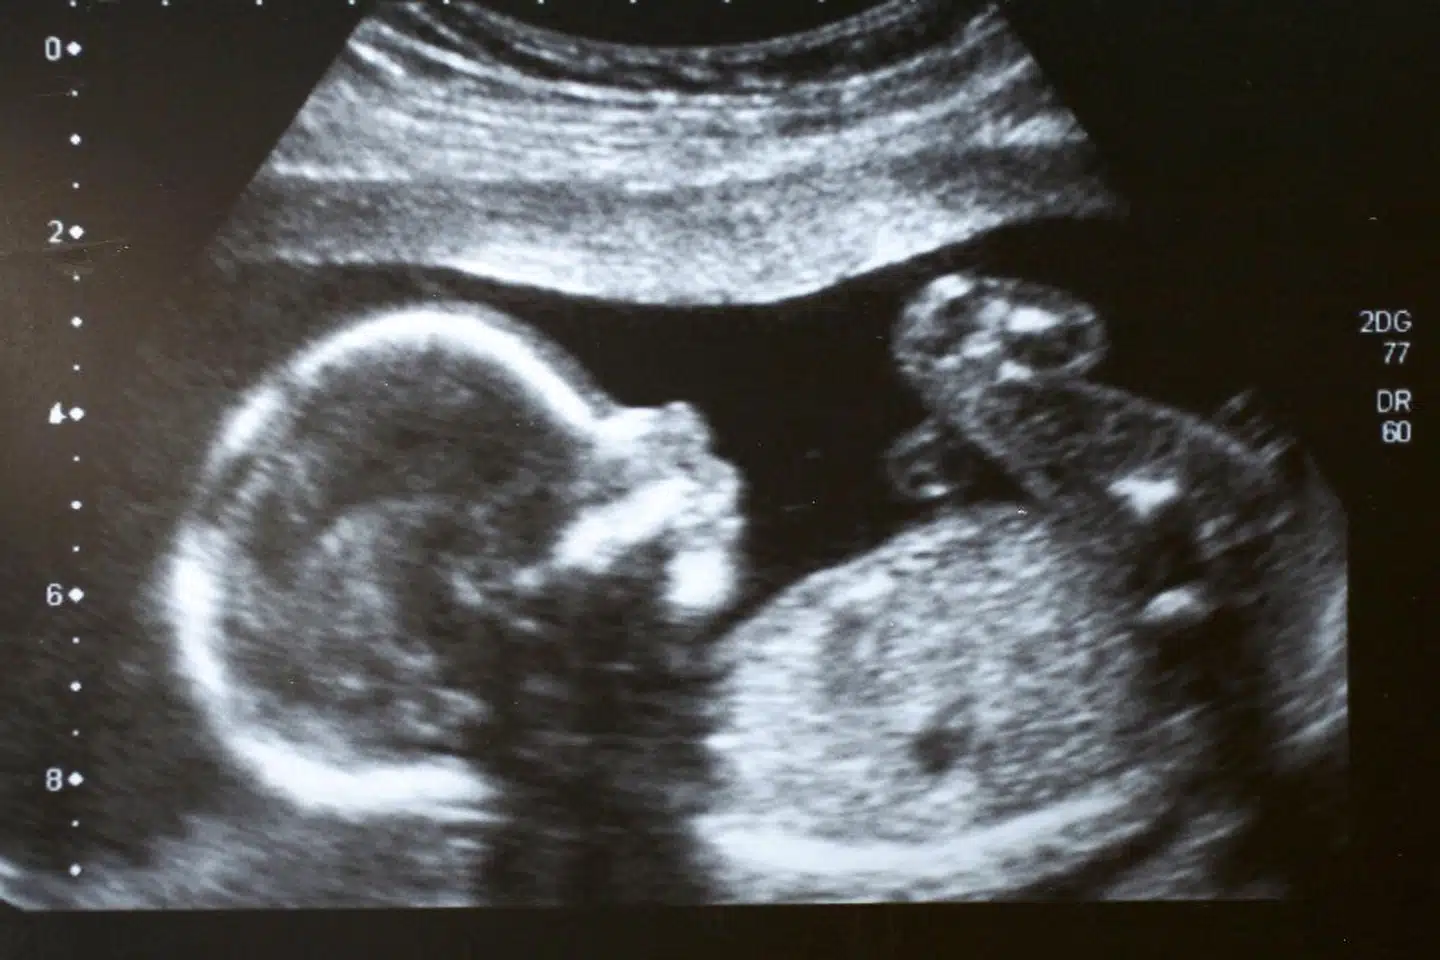

Men er et samfund ligestillet, når kun kvinderne kan føde og amme, og kun mænd kan stå op og tisse, mens deres diskriminerende store muskelmasse slapper af? Hvor fertilitetsvinduet for kvinders vedkommende lukker sidst i 30erne, mens mænd kan formere sig lystigt, til de dør?